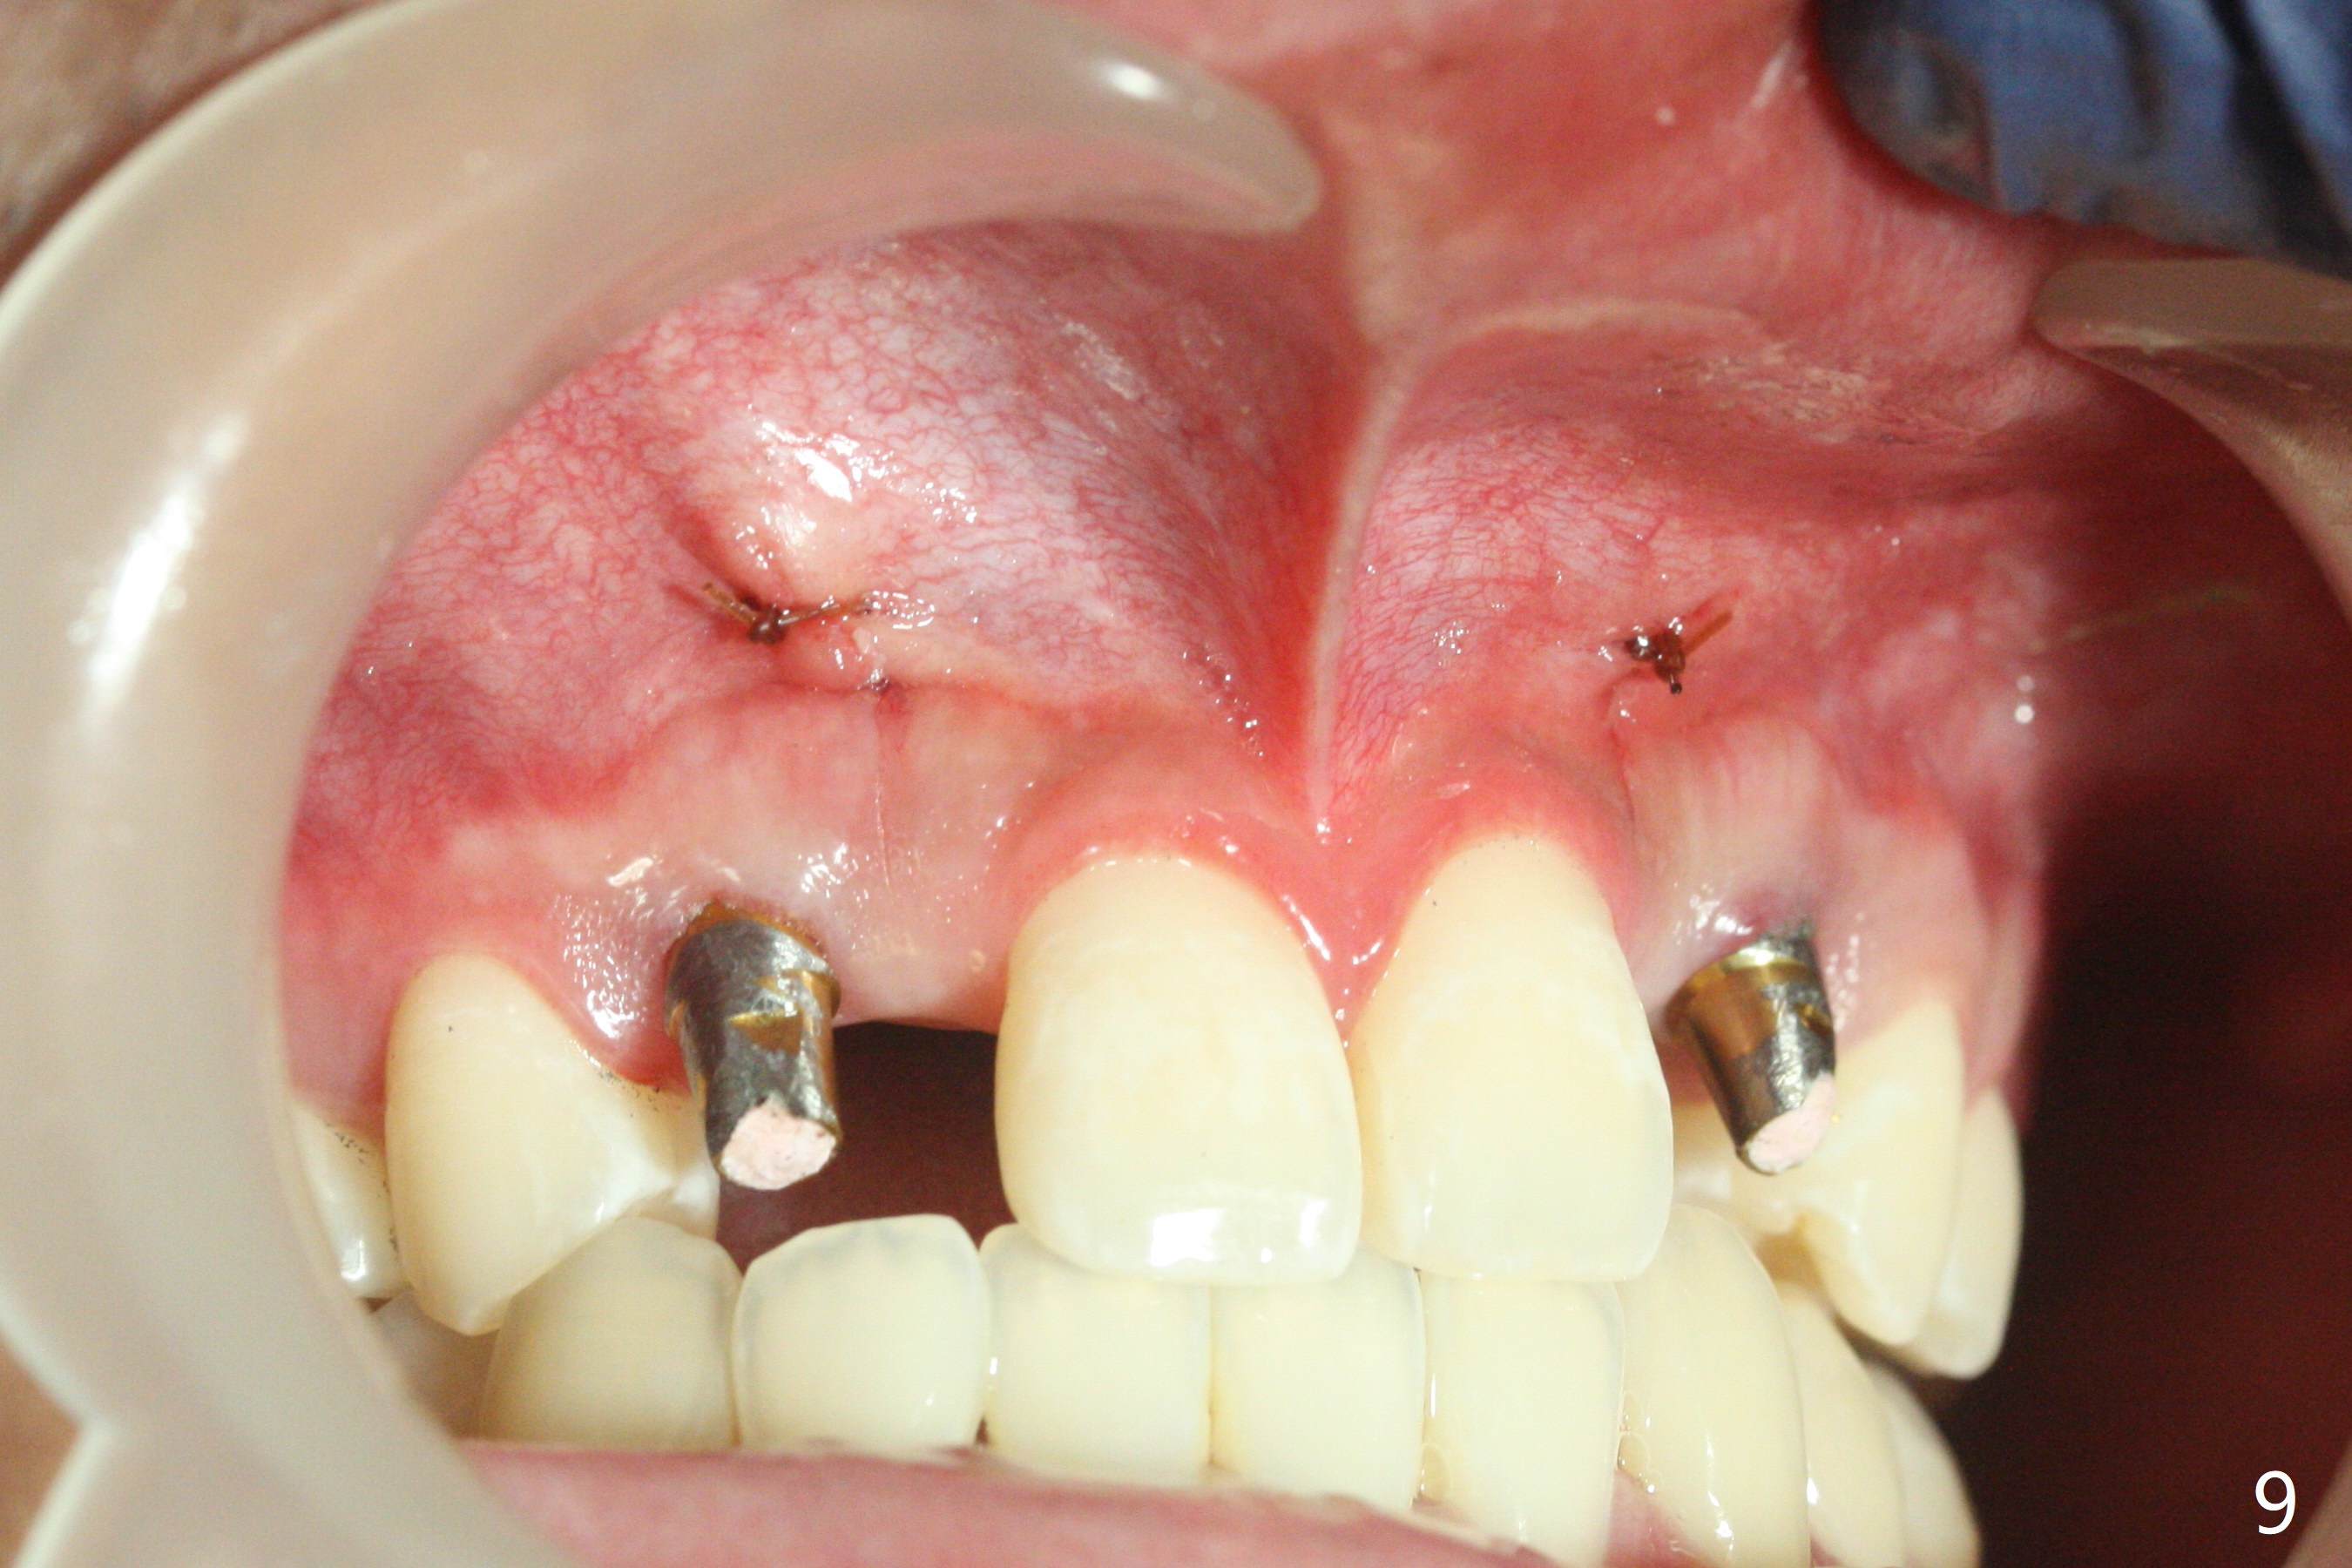

18岁男,本月底到外州上大学,急于十九岁前完成治疗,保险可以多付些。术前检查显示双侧尖牙(图一,二 6,11)根尖,侧切牙牙槽嵴萎缩(*),尖牙、侧切牙之间颊侧做垂直切口,骨膜下潜行分离,在尖牙根尖隧道植骨,然后使用导板,植入窄植体(图四至六),接近或者穿过上颌窦底板(图三,四箭头),骨粉(粘性骨块做的不成功,图五,六 *)好像覆盖暴露的螺纹。再次补充隧道骨粉后,放置修复基台(图七,八),调整后(图九),取模做临时悬臂桥,临床上有些困难分配尖牙,侧切牙比例。术后4个月左侧植体愈合正常(图十,十一),而右侧感染。